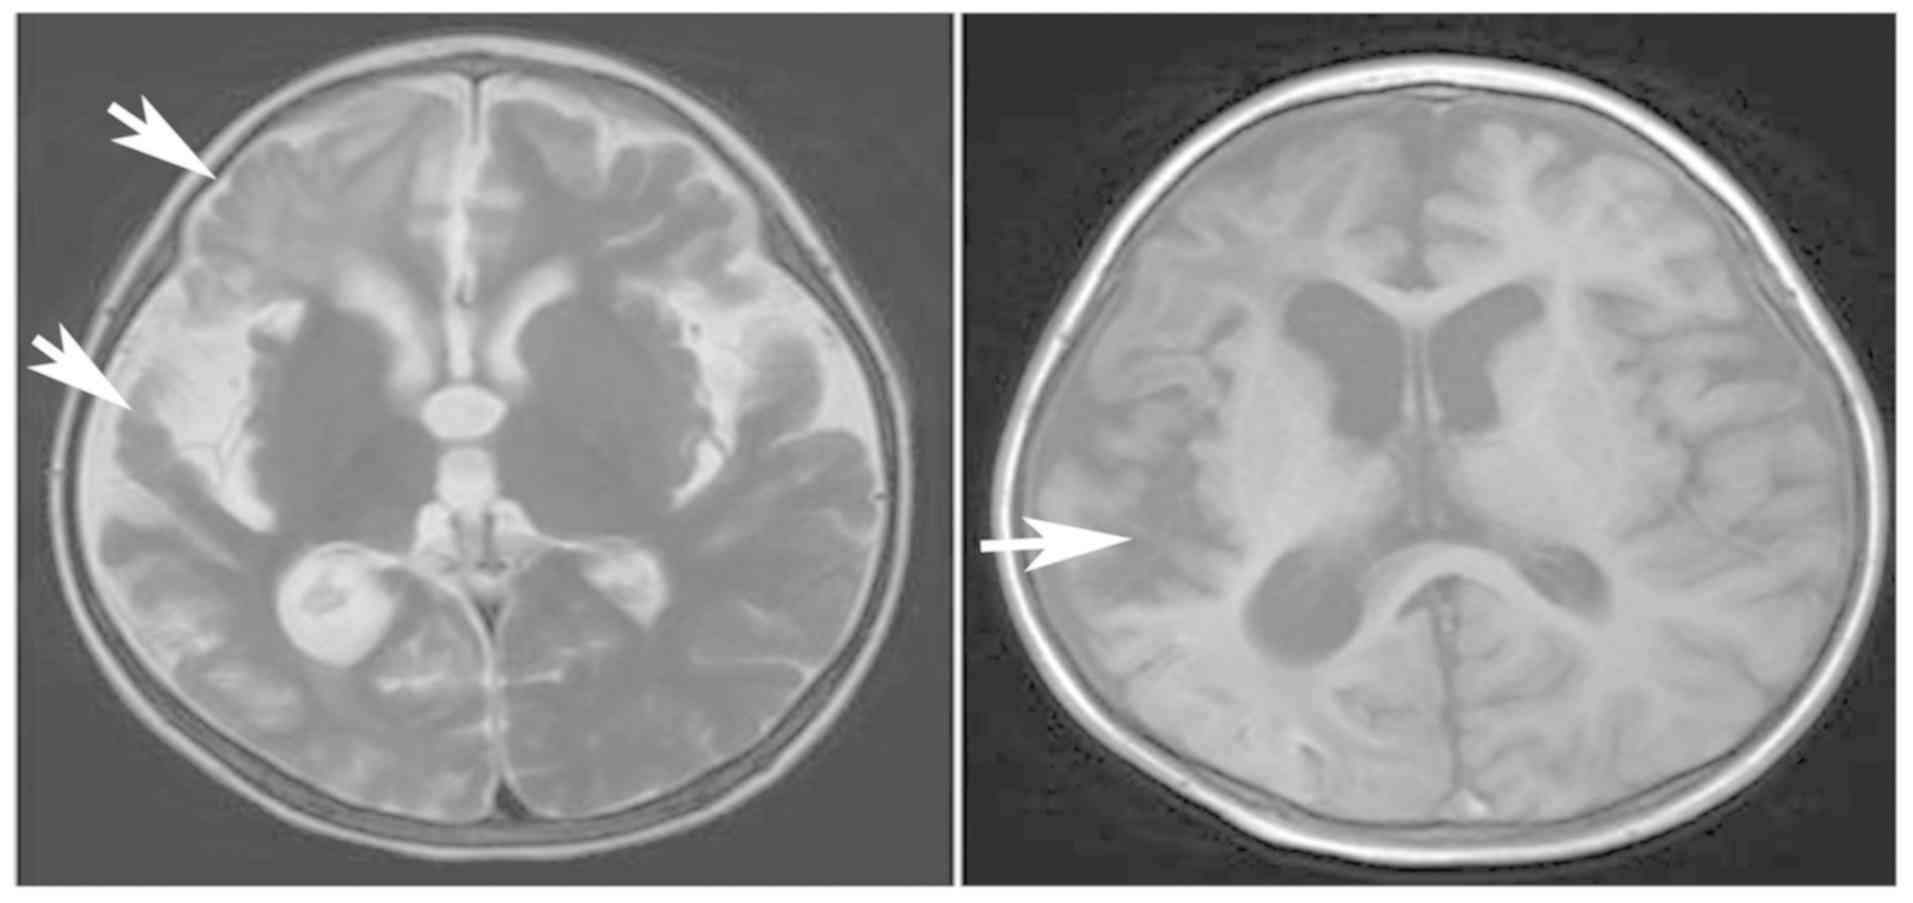

Primary carnitine deficiency in two sisters with intractable epilepsy and reversible metabolic cardiomyopathy: Two case reports

Primary carnitine deficiency (PCD) is a disorder of the carnitine cycle that results in defective fatty acid oxidation. When carnitine cannot be transported into the cells, fatty acid oxidation is impaired, resulting a variety of symptoms, such as chronic muscle weakness, cardiomyopathy, hypoglycemia and liver dysfunction. The clinical manifestations and outcomes of different cases with PCD vary among patients. The present case report focused on two sisters with PCD. The younger sister presented with intractable epilepsy, and the older sister presented with reversible metabolic cardiomyopathy. Potential mutations in the SLC22A5 gene were investigated within the family, and a nonsense mutation [c.760C>T (p.R254X)] was identified in four family members. The two sisters harbored homozygous mutations, whereas their parents presented heterozygous mutations. Metabolic disease screening revealed low plasma free carnitine levels (<5 µmol/l) in the two sisters. The plasma free carnitine levels of their parents were normal, and they were asymptomatic. PCD in the two patients was managed using oral levocarnitine. The metabolic cardiomyopathy of the older sister improved following 3 months of treatment. However, the epilepsy of the younger sister was recurrent with oral antiepileptic therapy lasting one year and eight months, and epilepsy was finally controlled following right cerebral resection. The present case report demonstrated that the clinical manifestations presented by patients with PCD within the same family were different. The results indicated that treatment with levocarnitine supplementation should be initiated as soon as possible before irreversible organ damage occurs. In addition, metabolic decompensation and cardiac muscle functions were improved following carnitine supplementation. The resection of the severely diseased unilateral brain combined with carnitine supplementation and antiepileptic therapy may be an effective treatment for PCD with intractable epilepsy complications.